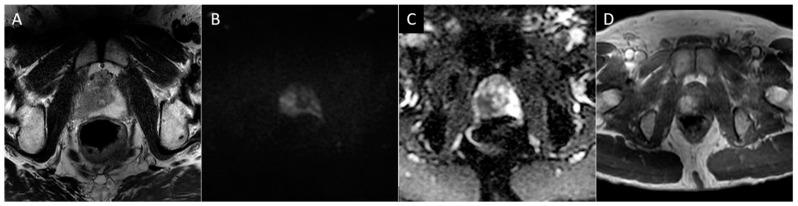

Contemporary Review of Multimodality Imaging of the Prostate Gland.

Tissue changes and the enlargement of the prostate, whether benign or malignant, are among the most common groups of diseases that affect men and can have significant impacts on length and quality of life. The prevalence of benign prostatic hyperplasia (BPH) increases significantly with age and affects nearly all men as they grow older. Other than skin cancers, prostate cancer is the most common cancer among men in the United States. Imaging is an essential component in the diagnosis and management of these conditions. Multiple modalities are available for prostate imaging, including several novel imaging modalities that have changed the landscape of prostate imaging in recent years. This review will cover the data relating to commonly used standard-of-care prostate imaging modalities, advances in newer technologies, and newer standards that impact prostate gland imaging.